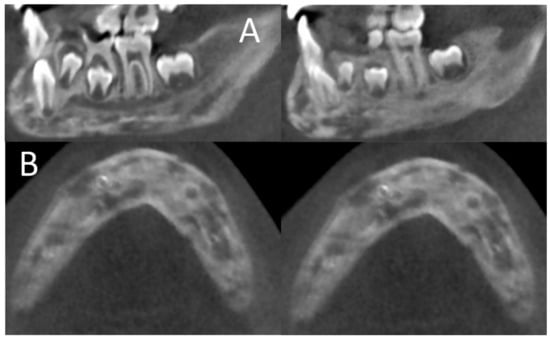

2.1. Initial Diagnosis and Initial Surgical Management